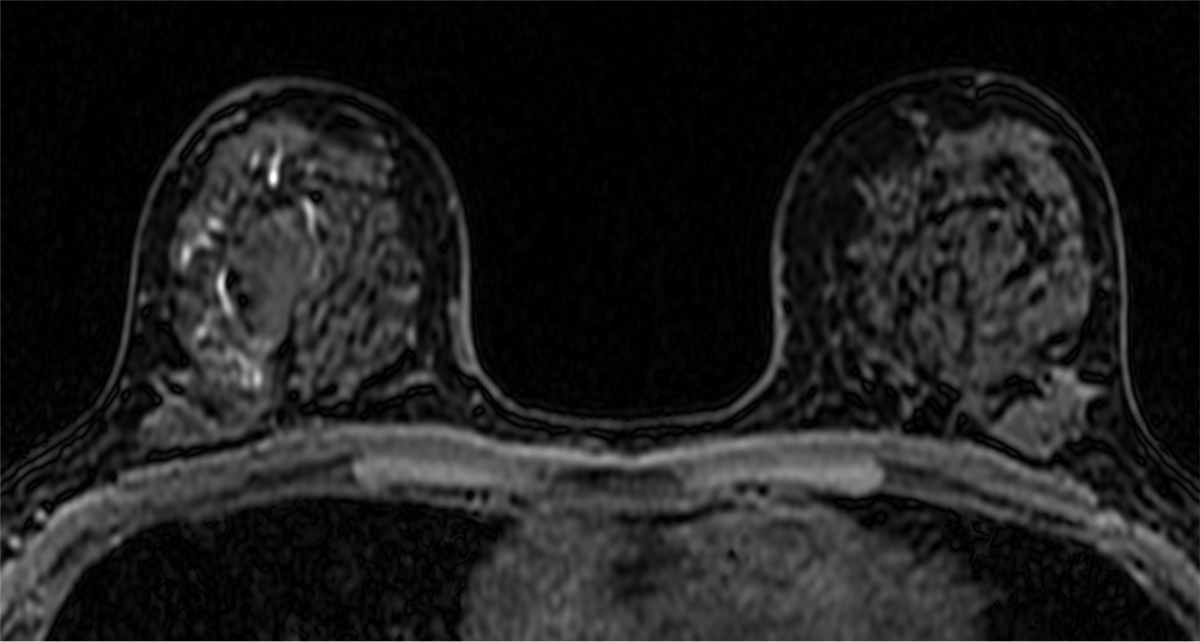

乳腺MRIは乳癌の広がりを高精度に診断できる。この症例においてもマンモグラフィーでは病変を指摘出来なかったが、MRIでは病変が明瞭に描出され、エコーで捉えられる領域よりも広範に及んでいる事が示された。3D解析を用いることでより俯瞰的な評価ができ、術式の選択や切除範囲の一助となった。

近年では、圧迫センシングなどの撮像技術の進歩によりUF-DCE MRIが可能となった。造影直後の超早期からの数秒毎の撮像を行うことで、乳腺組織とのコントラストを高め、血流豊富な腫瘍と腫瘍関連血管の評価に優れている。使用する造影剤量の増加や撮像時間の延長なく、良悪性の鑑別や薬物療法の治療効果予測に役立つと報告されており、更なる臨床応用が期待されている。